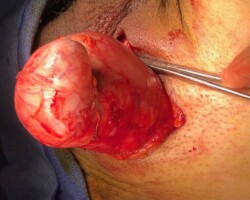

Resection of large retroperitoneal sarcoma including right and transverse colectomy and right hepatectomy